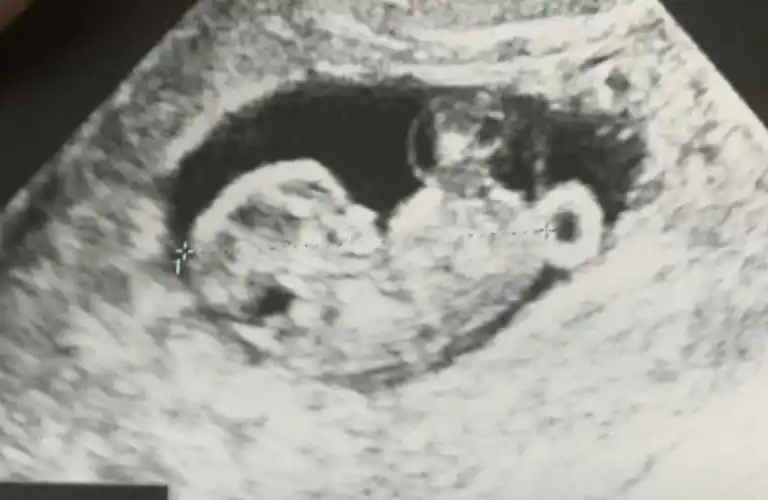

7月26日做的b超检查证实欢欢怀孕了,胚胎长3.4厘米.

然而不幸的是, 12 周时超声显示单绒双羊三胎妊娠,其一羊膜囊内为正常

3,一孕妈在12周的b超检查中,发现小胎儿正顽皮地上窜下跳,逗得她不禁